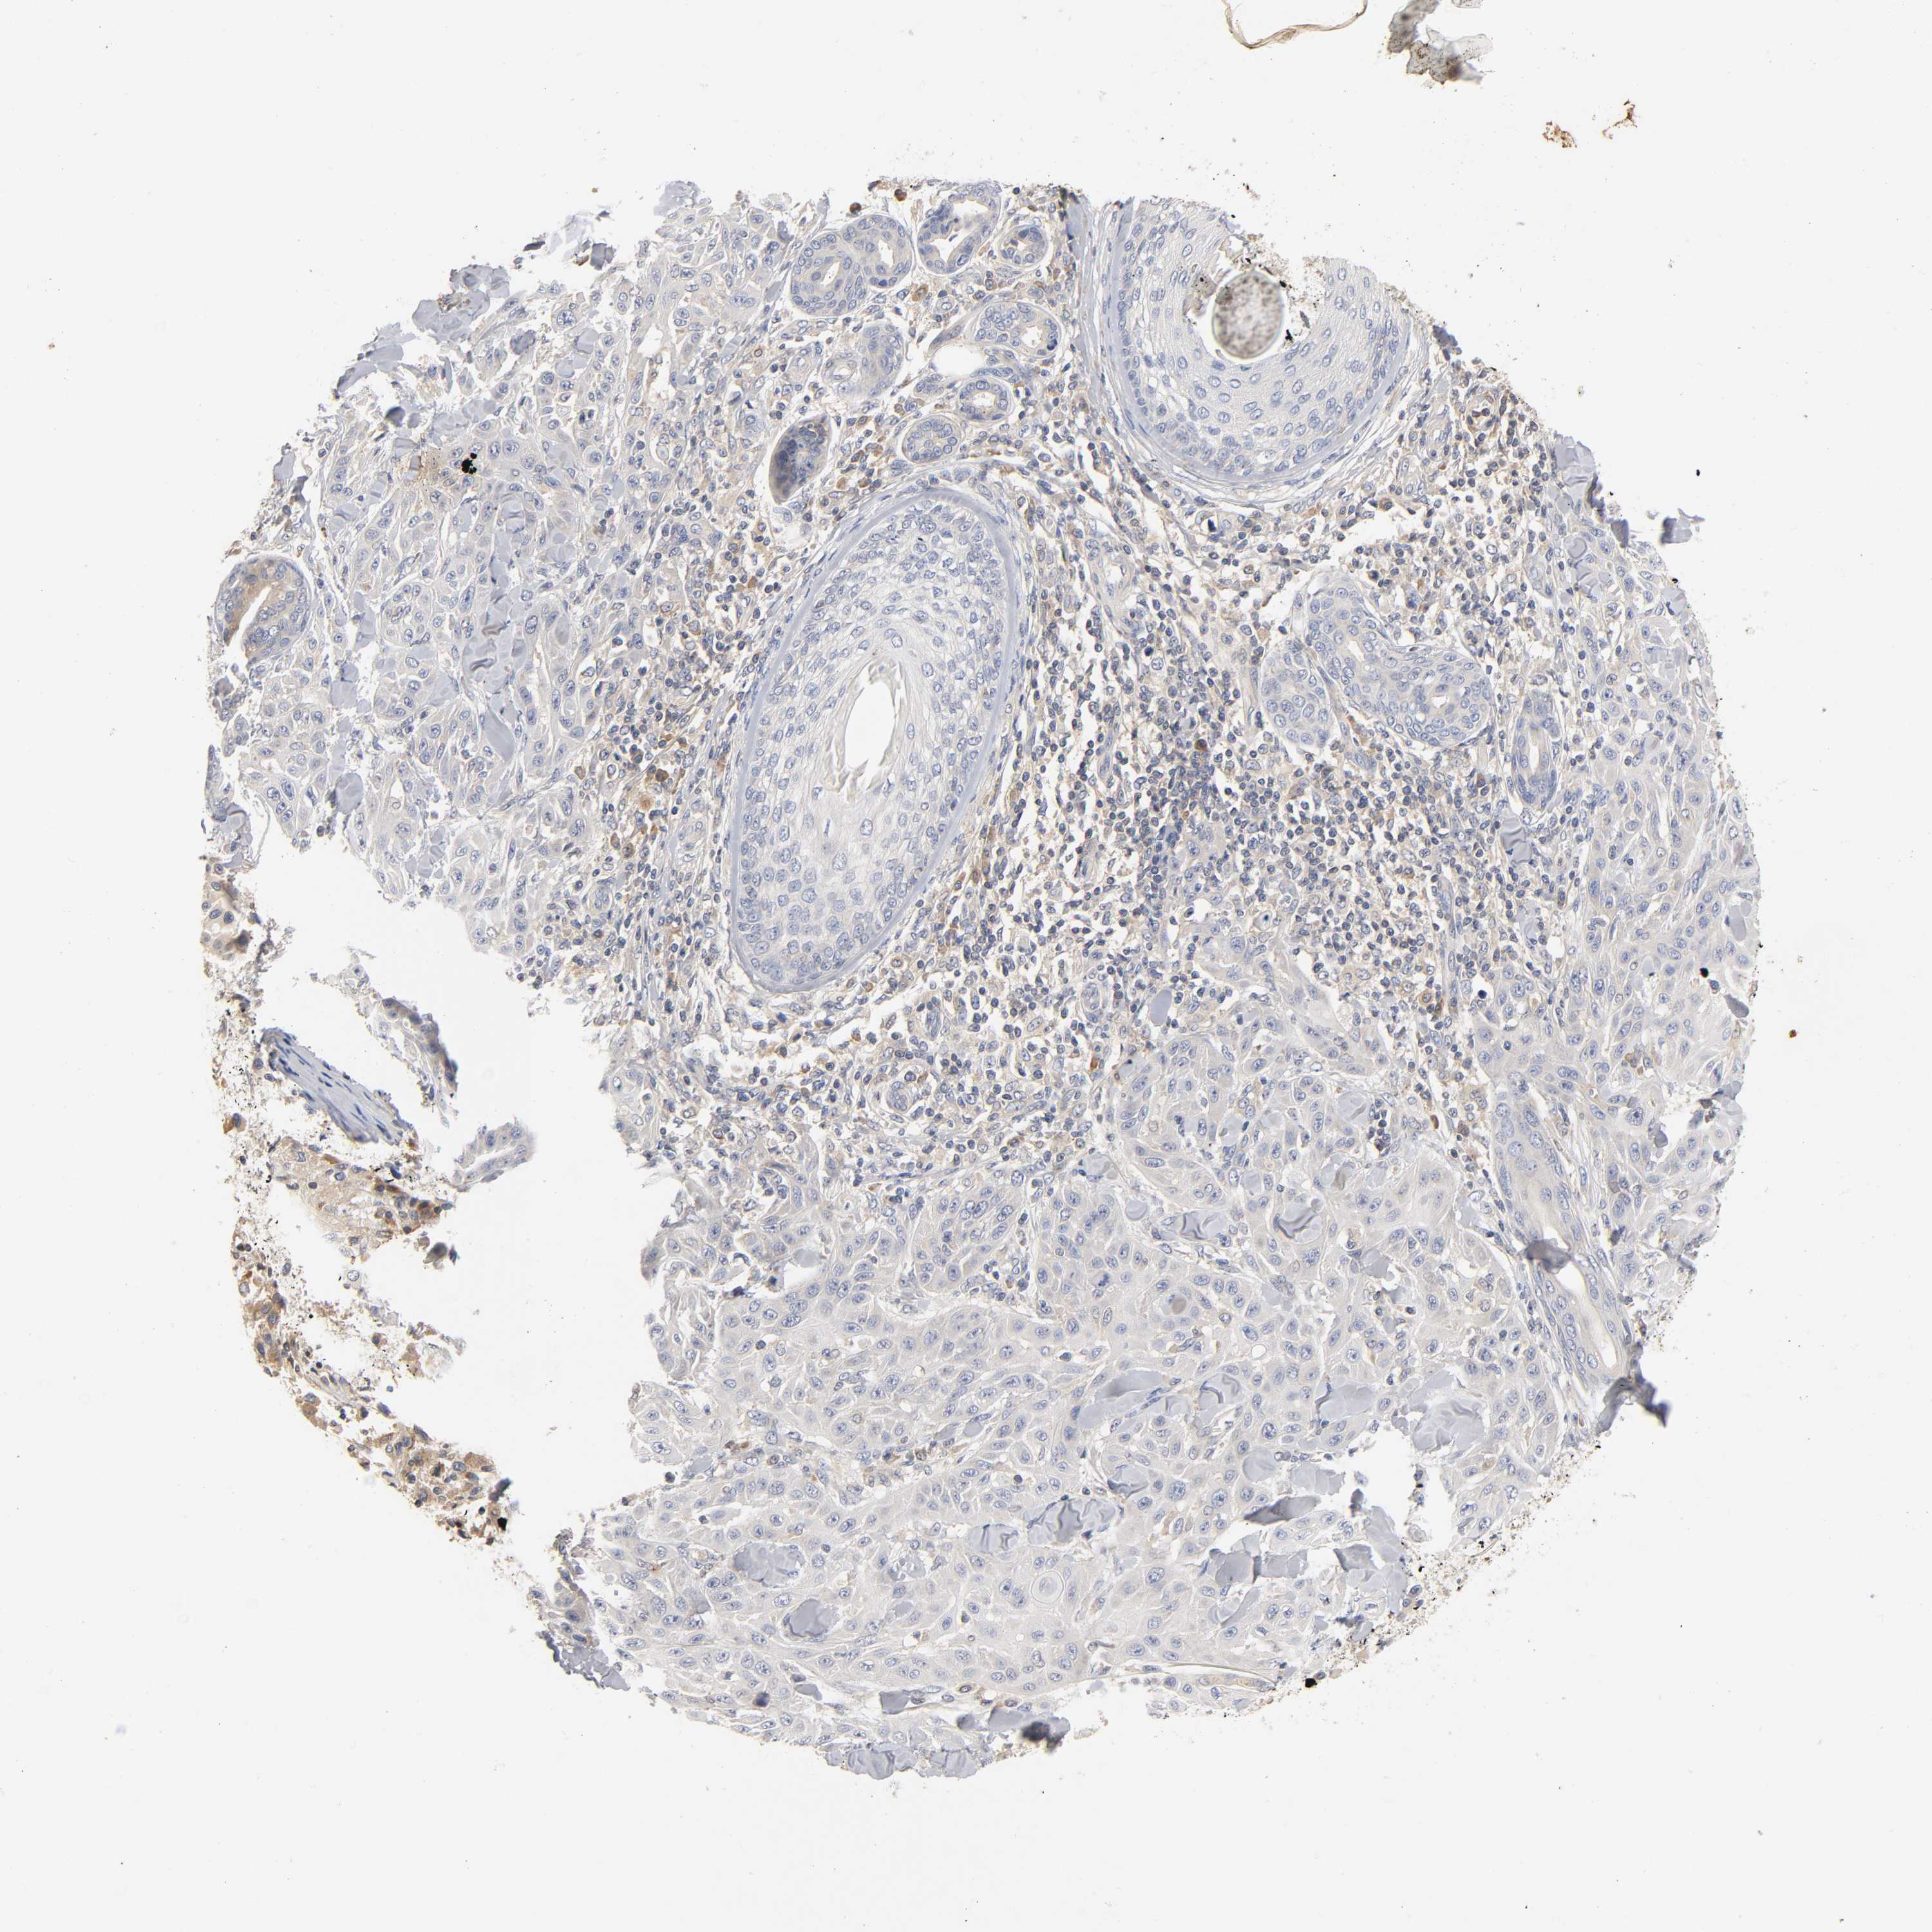

SKIN CANCER - Protein expressioni

A mouse-over function shows sample information and annotation data. Click on an image to view it in a full screen mode. Samples can be filtered based on level of antibody staining by selecting one or several of the following categories: high, medium, low and not detected. The assay and annotation is described here.

Antibody stainingi

Antibody staining in the annotated cell types in the current human tissue is reported as not detected, low, medium, or high, based on conventional immunohistochemistry profiling in selected tissues. This score is based on the combination of the staining intensity and fraction of stained cells.

Each image is clickable and will lead to virtual microscopy that enables deeper exploration of all samples and also displays staining intensity scores, fraction scores and subcellular localization as well as patient and tissue information for each sample.

Antibody CAB005052

Staining

High

Medium

Low

Not detected

Intensity

Strong

Moderate

Weak

Negative

Quantity

>75%

75%-25%

<25%

None

Location

Nuclear

Cytoplasmic/membranous

Cytoplasmic/membranous,nuclear

Squamous cell carcinoma, NOS

Basal cell carcinoma